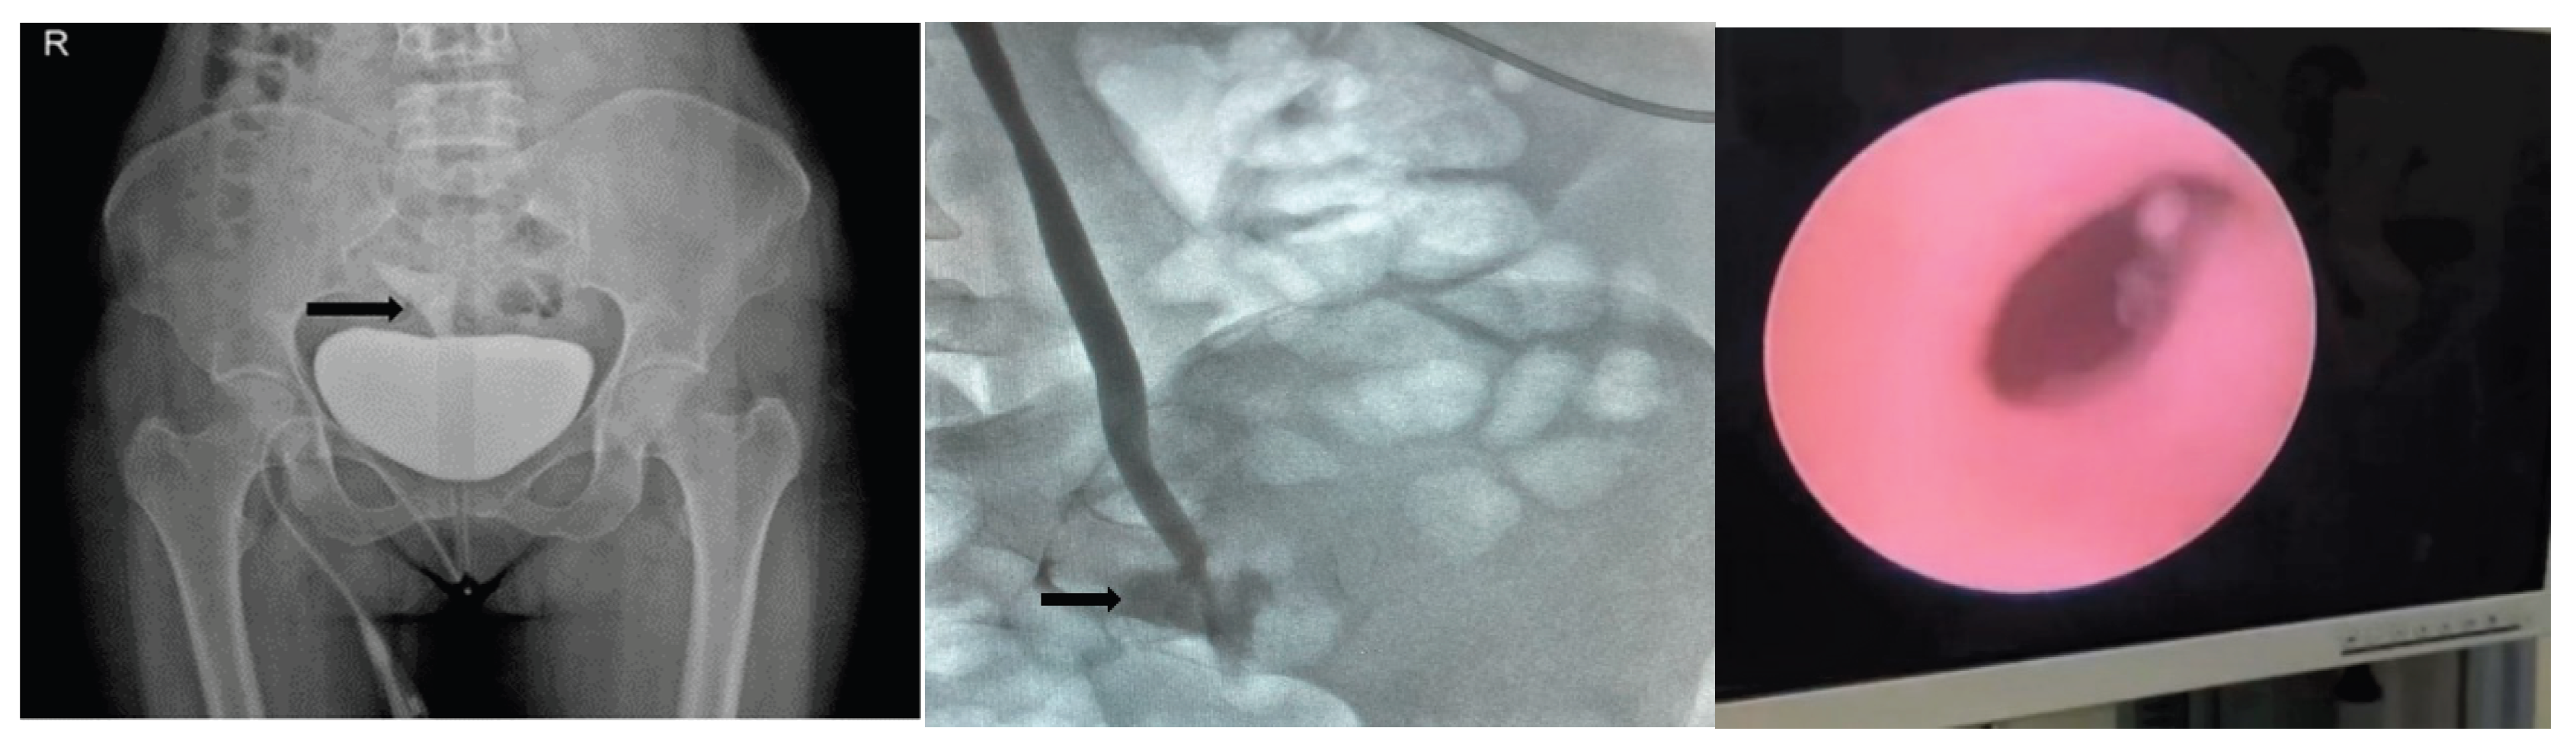

| CT urogram | 20 (9.0) |

| Cystogram + CT urogram | 20 (9.0) |